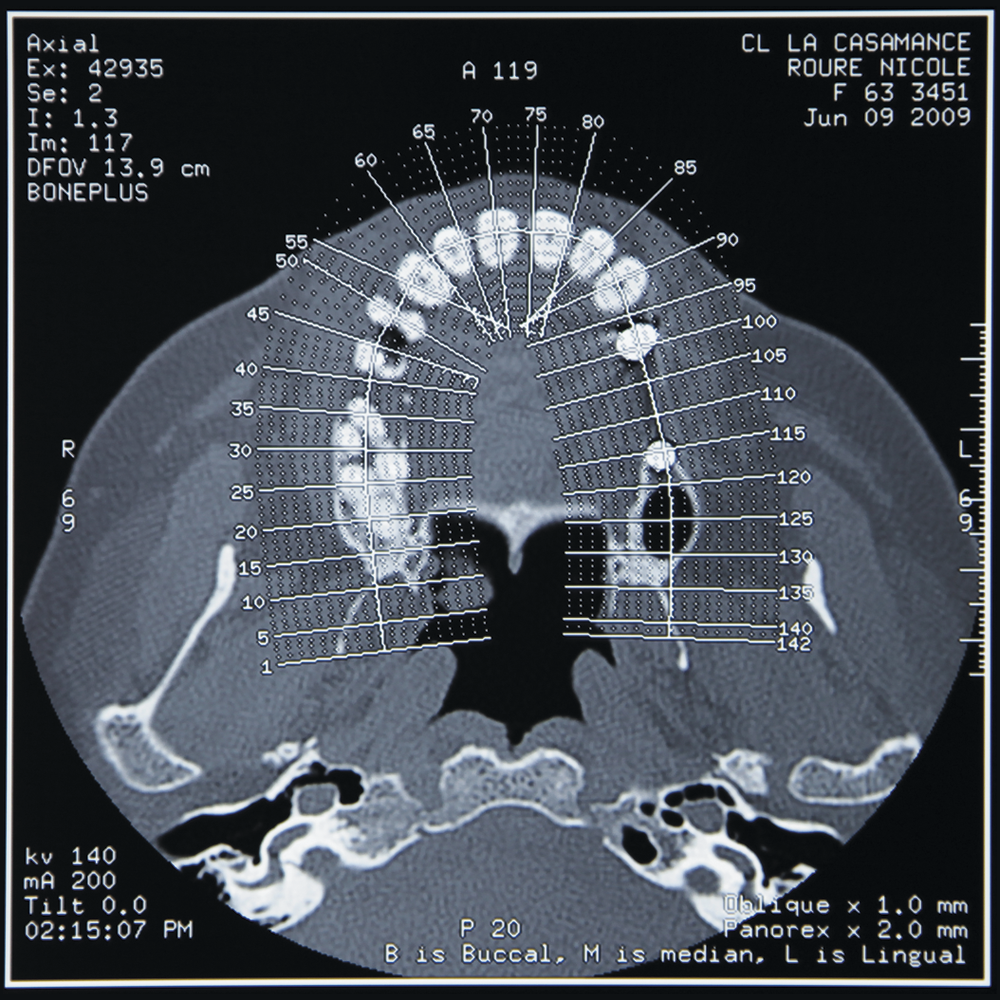

- Imagerie médicale (de la panoramique au dentascanner …)

- Interprétation imagerie médicale

Les formations se déroulent au sein de la clinique La Casamance à Aubagne et permettent d’acquérir des compétences pratiques directement applicables en cabinet.